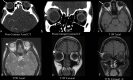

The lacrimal gland is a bilobed serous gland located in the superolateral aspect of the orbit. Lacrimal system pathologies can be broadly divided into pathologies of the lacrimal gland and those of the nasolacrimal drainage apparatus. These include distinct congenital, infectious, inflammatory, and benign, indeterminate, and malignant neoplastic lesions. Trauma and resultant fractures affecting lacrimal drainage apparatus is not part of this review; only non-traumatic diseases will be discussed. CT is the initial modality of choice because of its ability to delineate lacrimal system anatomy and demonstrate most lacrimal drainage system abnormalities and their extent. It also assesses bony architecture and characterizes any osseous changes. MRI is helpful in further characterizing these lesions and better assessing involvement of the surrounding soft tissue structures. In this pictorial review, we will review the anatomy of the lacrimal system, describe CT/MRI findings of the common and uncommon lacrimal system abnormalities and discuss relevance of imaging with regards to patient management.